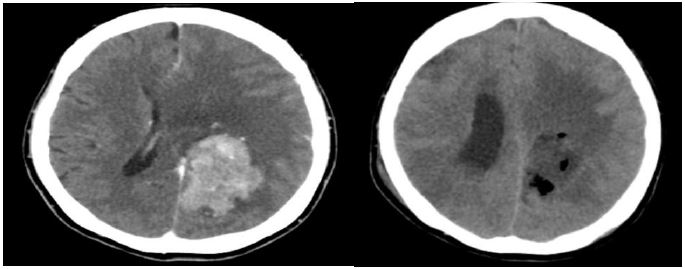

A 50 years old lady with underlying hypertension and dyslipidemia on treatment, presented with symptoms of right sided body weakness progressively worsening over past one year associated with loss of appetite and loss of weight. She denies any headache, loss of consciousness or fitting episode. Neurologically, muscle power over right upper limbs and lower limbs were 4/5. Muscle tone, reflexes and sensation were otherwise unremarkable. computed tomography (CT scan) brain and Magnetic Resonance Imaging (MRI) brain done suggestive of left parasaggital meningioma with extra axial mass from left fronto-parietal extending to occipital lobe measuring 4.9 x 3.6 x 7.1 cm associated with perilesional edema and midline shift. She was started on Intravenous (IV) Dexamethasone 4 mg TDS, IV Phenytoin 750 mg loading then subsequently 300 mg ON. Posted for left frontoparietal craniotomy and tumor excision. Induction was smooth with target controlled infusion (TCI) Remifentanil and Sevoflurane inhalational. She was intubated with Endotracheal Tube (ETT) sized 7.5 mm and anchored at 20 cm, otherwise uneventful. Left radial artery was cannulated for invasive blood pressure monitoring with adequate intravenous access. She received IV Dexamethasone 8 mg Q8H, IV Tranexamic Acid 1g Q8H, and IV Cloxacillin 1 g Q4H during the operation.

Figure 1: CT brain image pre operative (left) vs post operative (right).